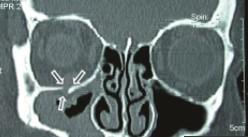

Alors enfaite une fracture du plancher de l'orbite c'est ça :

plancher orbite.jpg

plancher orbite.jpg (11.8 Kio) Vu 197 fois

Le plancher de l'orbite est facturé, donc l'œil compris dans l'orbite ne va plus être positionner correctement.

Donc tu vas avoir une incarcération du muscle droit inférieur (donc le muscle droit que dans 1 direction) dans le trait de fracture. Ce muscle extrinsèque sera bloquée et va entrainer une diplopie verticale :)